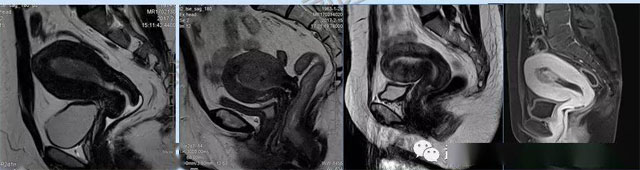

妇科疾病常常让女性陷入了焦虑。主要是这类疾病妇女有难言之隐,症状隐匿,病情复杂。磁共振体检车的金光火眼能力可以破解各种妇科难题。哪些情况需要使用磁共振检查,检查过程是否有不适。这些都是可以解决的。例如子宫常见疾病的磁共振诊断。

磁共振VS传统检查:有这些优势?无辐射安全系数高,磁共振没有电离辐射,适合备孕跟孕妇检查。它对软组织有高清的成像效果,可以清晰的看到子宫各层的结构。可以识别细小的肌瘤,早期的癌症肿瘤。可以发现其他设备难以检查到的深部子宫内膜异位结节。多序列成像和增强扫描检查,判断肿瘤的良性准确率高达90%以上。